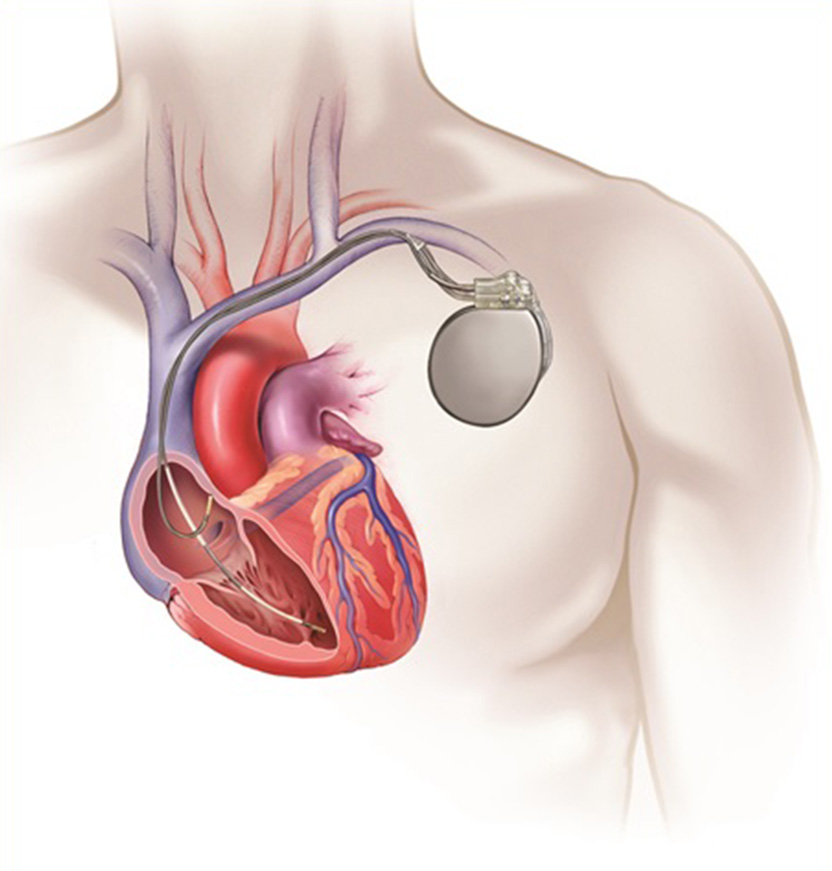

Value added benefits of the Pacemaker Procedure Biventricular:

Value added benefits of the Pacemaker Procedure Double Chamber:

Value added benefits of the Permanent Pacemaker Implantation: